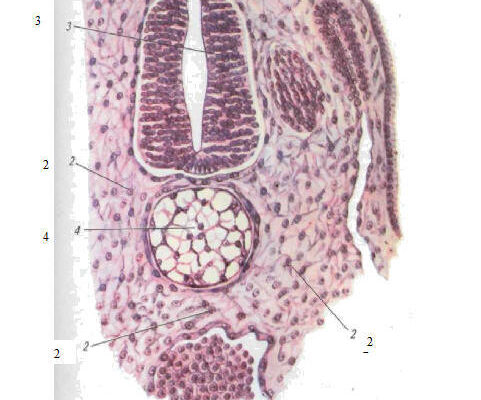

Суть Мезенхіми

Чесно, це складне божевілля, але в чому суть? Мезенхіма — це мультипотентна стромальна клітинна тканина, яка присутня ще на етапі ембріона людини. Простими словами, вона складається з клітин, які можуть перетворитися в будь-яку сполучну тканину. Це справжня вавка у світі клітин. Думаєте, просто? Аж ніяк.